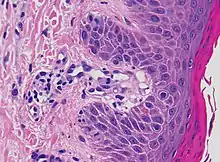

Lichen nitidus

• Localized granulomatous lymphohistiocytic infiltrate in an expanded dermal papilla

• Thinning of overlying epidermis and downward extension of the rete ridges at the lateral margin of the infiltrate, resulting in a typical "claw clutching a ball" appearance.[10]